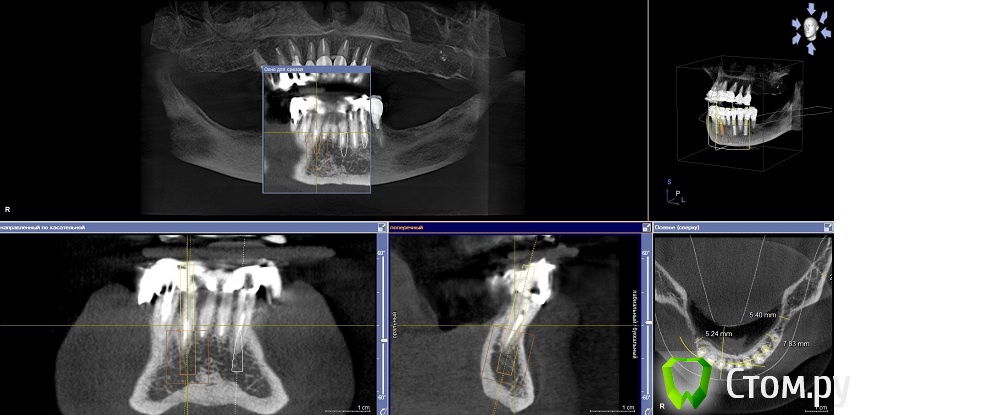

Dr.Sham Опубликовано 14 октября, 2014 Поделиться Опубликовано 14 октября, 2014 (изменено) Планируется удаление всех зубов на НЧ. Пациентка хочет несъемную конструкцию.Вот нарезка.Планируется имплантация Ankylos в позициях 46, 44, 42, 32, 34, 36.В боковых отделах дефицит всего.Думаю удалить зубы через один, чтобы на них временная конструкция держалась, а в промежутках имплантаты.В переднем отделе узко, либо узкие ФДМки, либо заглушка и в овоид край времянок или закрыть свободным трансплантатом.Что думаете?В боковых отделах вопрос...короткие имплантаты и НКР? От сложной костной пластики пациентка отказывается категирочески. Сверху пациентка так же хочет несъем. Поэтому все на 4-х, наверное, не самамя удачная конструкция здесь. Зубы сохранить никак, преп под десной местами по 3 мм. ну и дентин весь мягкий. Изменено 14 октября, 2014 пользователем Dr.Sham Ссылка на комментарий

Mane Опубликовано 15 октября, 2014 Поделиться Опубликовано 15 октября, 2014 Добрый вечер. Можно вариант Дмитрия. А можно и : Ваксап 12 зубов на н/чОртопедический шаблон на н/ч Операция: удаляете все сразу 4 имплантата 34-32-42-44 - по длиннее - чтоб торк точно был. В боковых отделах поставьте коротыши и НКР по толщине сделайте. перед установкой имплантатов, как сказал Дмитрий, выровняйте гребень во фронтальном отделе - чтоб с боковыми отделами не было большого перепада - коромысла. Срузу после операции нагружайте эти 4 имплантата несъемной конструкцией лабораторного изготовления. Если требуется, можно и по десне поработать в первую операцию. Удачи. На анкилозе есть же коротыши! 4 Ссылка на комментарий

Дмитрий Никитюк Опубликовано 15 октября, 2014 Поделиться Опубликовано 15 октября, 2014 Мысли в слух: планировать нужно, исходя из будущего протезирования обеих челюстей. Я посмотрел на верх и, учитывая возраст пациентки (69 лет), понимаю, что вряд ли там будет синус и 8 имплантатов. Там скорее всего будет или съёмный протез, или максимум 6 имплантатов (пусть топикстартер поправит, если не так). Поэтому на н.ч. вполне достаточно 4 импланта. Два из них под углом 30 °, с выходом платформ на область вторых премоляров, два других между ними (нет разницы в каких позициях). Почему не больше имплантатов? А зачем больше? Лучше эти деньги потратить на довольно дорогостоящую, но очень продуманную систему SmartFix. Каждый дополнительный имплантат будет лишь удорожать конструкцию и усложнять технологический этап. А 12 зубов на н/ч вполне достаточно. Ну и не будем забывать, что нижняя челюсть во время функции меняет геометрию, что вынуждает нас при дистально расположенных опорах делить конструкцию на части.Также от будущей судьбы верхнего зубного ряда зависит и материал постоянной конструкции на н/ч, но это будет потом. 1 Ссылка на комментарий

Dr.Sham Опубликовано 15 октября, 2014 Автор Поделиться Опубликовано 15 октября, 2014 Добрый вечер. Можно вариант Дмитрия. А можно и : Ваксап 12 зубов на н/чОртопедический шаблон на н/ч Операция: удаляете все сразу 4 имплантата 34-32-42-44 - по длиннее - чтоб торк точно был. В боковых отделах поставьте коротыши и НКР по толщине сделайте. перед установкой имплантатов, как сказал Дмитрий, выровняйте гребень во фронтальном отделе - чтоб с боковыми отделами не было большого перепада - коромысла. Срузу после операции нагружайте эти 4 имплантата несъемной конструкцией лабораторного изготовления. Если требуется, можно и по десне поработать в первую операцию. Удачи. На анкилозе есть же коротыши!Спасибо за отзыв. Теперь понял про коромысло ) 6,6 мм должны быть, но их нет в РФ. А 8 мм - уже не коротыши, при том, что коллеги рекомендуют на 2 мм заглублять. Ссылка на комментарий